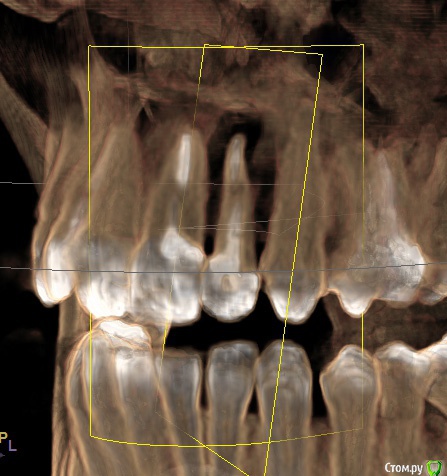

Ankazabolevshaya Опубликовано 28 мая, 2016 Поделиться Опубликовано 28 мая, 2016 Здравствуйте, уважаемые врачи! Очень сильно нуждаюсь в вашей помощи. В 2013 мне лечили два передних зуба (клык и передний). Пломбировали каналы, но коронки не ставили. Этой зимой я почувствовала боль в передних зубах в районе челюсти. Раздражение в дёснах. Резь. Потом вылез какой-то пупырь на десне. Я думала, что это стоматит. Не верила тем, кто мне говорил про нужность обзорного снимка. Признаю свою глупость. Теперь, после КТ оказалось что у меня сломаны эти каналы, а под левым клыком пустота. А пупырь, как мне сказали - это выход свища.Мне предложили зуб удалять. Как-то восстанавливать эту пустоту. Потом делать имплантацию. Есть ли сегодня технологии, позволяющие восстанавливать это пространство под зубом без его удаления, с последующей коронкой на него? И ещё один вопрос: могло ли все это случится из-за какой-нибудь заразы, занесенной во время лечения этих двух зубов в 2013г. ? Так же был момент ранения слизистой левой ноздри, как раз над свищем, который на десне. Просто очень часто слизистая иссыхала в одном месте и я травмировала слизистую. Буду очень благодарна за ответ. От меня в клинике ждут решения, а я переживаю, что улыбка испортится с искусственным зубом. Зуб этот свой очень люблю. Анна. Ссылка на комментарий

red_butler Опубликовано 28 мая, 2016 Поделиться Опубликовано 28 мая, 2016 Спасибо! Можете пояснить, Вы думаете, что зуб можно спасти? если судить только по снимкам, то да 1 Ссылка на комментарий

red_butler Опубликовано 29 мая, 2016 Поделиться Опубликовано 29 мая, 2016 а скажите, как по Вашему, это киста прикорневая? Или челюсть разрушена? Нужно восстановление челюсти? это не важно и корень ведь сломан, поставить под коронки всё равно можно? перелома не увидел И еще последнее, как Вы относитесь к процедуре - депофорез? В моём случае стоит в эту торону смотреть? бесполезно 2 Ссылка на комментарий